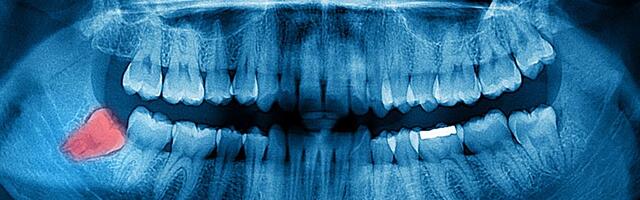

Quello dei denti del giudizio è un problema per molte persone dal momento che essi non sembrano avere altra funzione che quella di intaccarsi, infettarsi e provocare, in generale, molto dolore. Non facilitano granché la masticazione, in compenso possono spostare gli altri denti e richiedere l’intervento dell’odontoiatra. Qualcuno potrebbe pensare che vengano inseriti in bocca dai dentisti per avere più pazienti e quindi una maggiore mole di lavoro per il più lungo tempo possibile. Sono dei denti rudimentali e nella maggior parte dei casi vanno estratti a causa dei diversi problemi che possono causare.